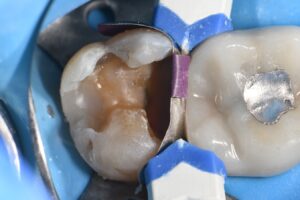

March 10, 2026 (Afternoon tea pics 2341.3: Kerr Simplishade | Rhondium DME | Garrison Dental Solutions – North America) Getting d o w n with DME. #RhondiumDME #KerrSimplishade #GarrisonCompositight Previous Post